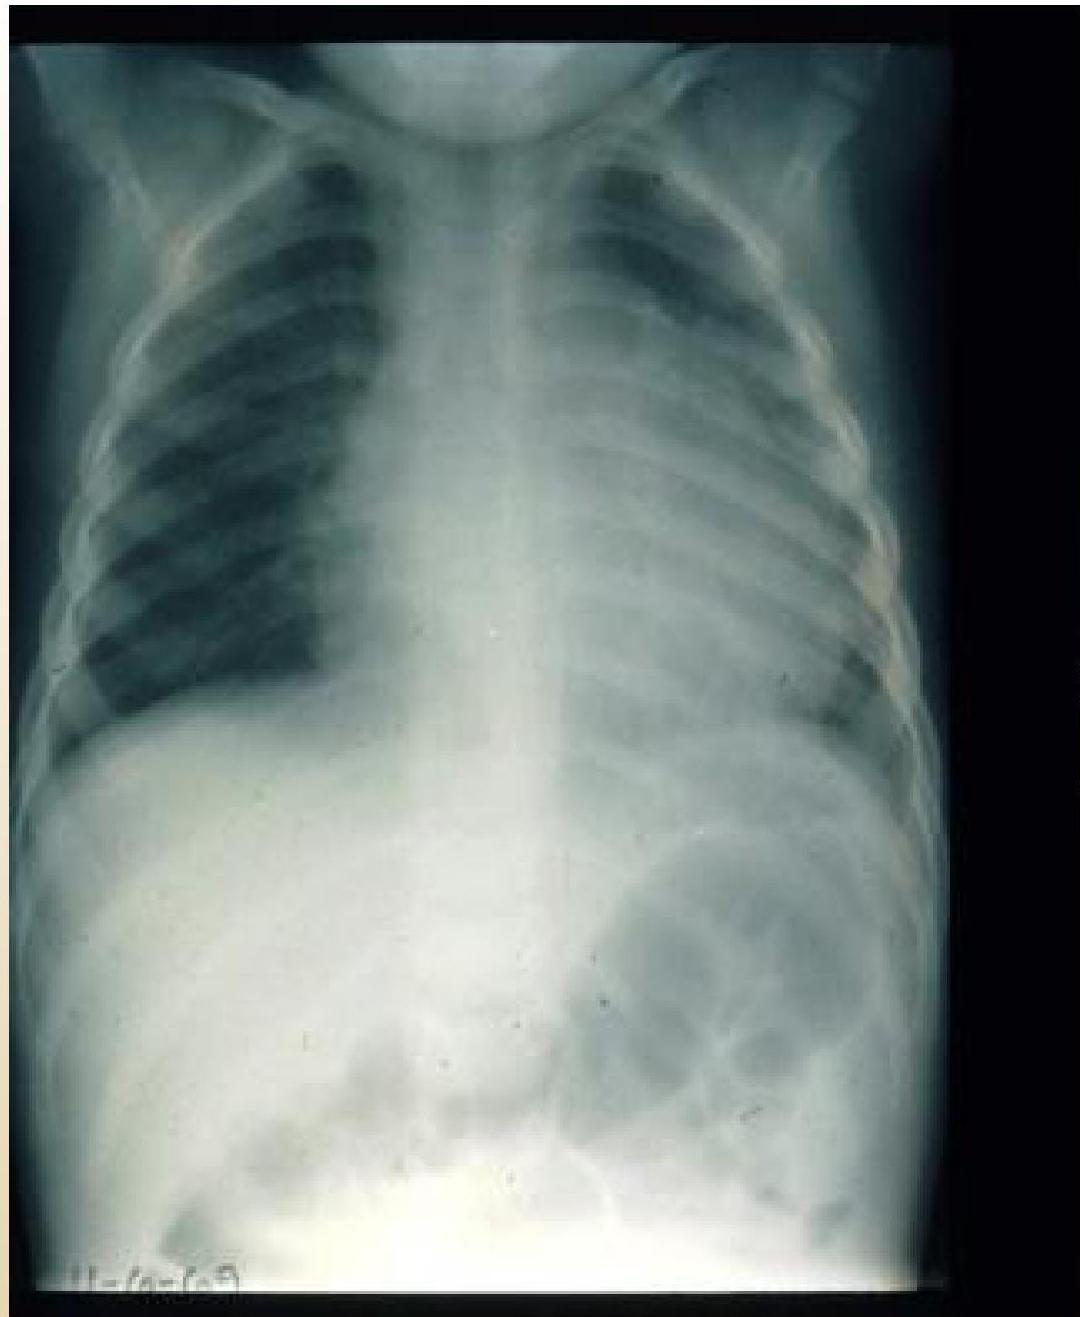

Pericardial Effusion:

X-RAY of child with pericardial effusion